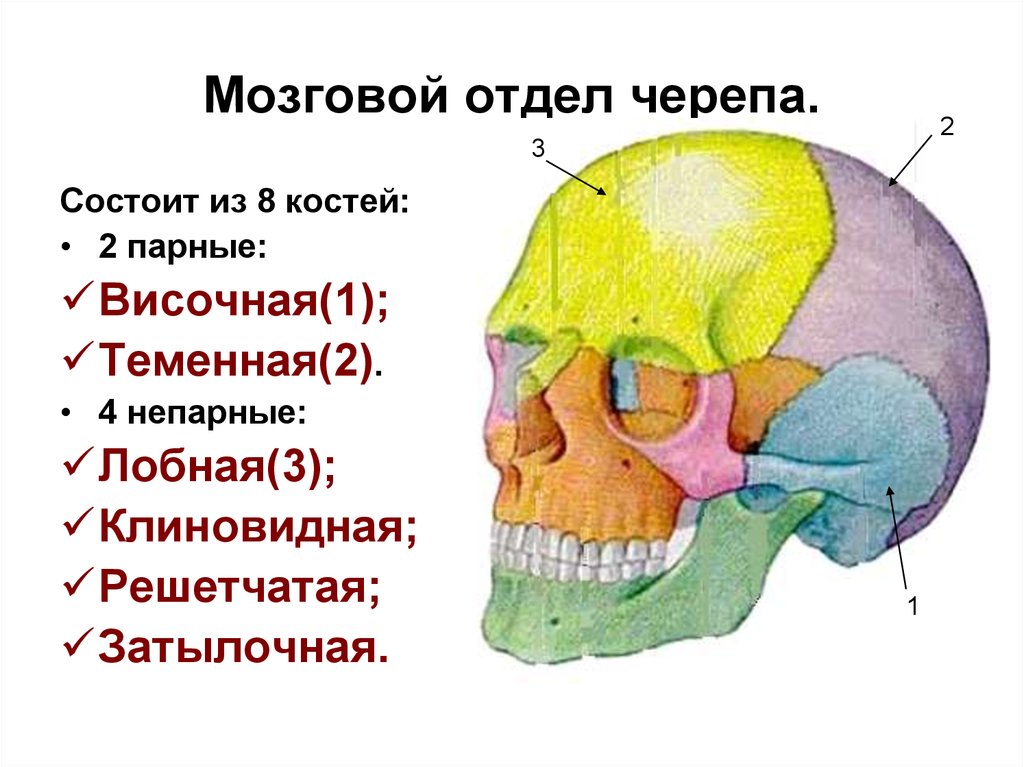

Анатомия детского черепа: Рентгеновские снимки и описание